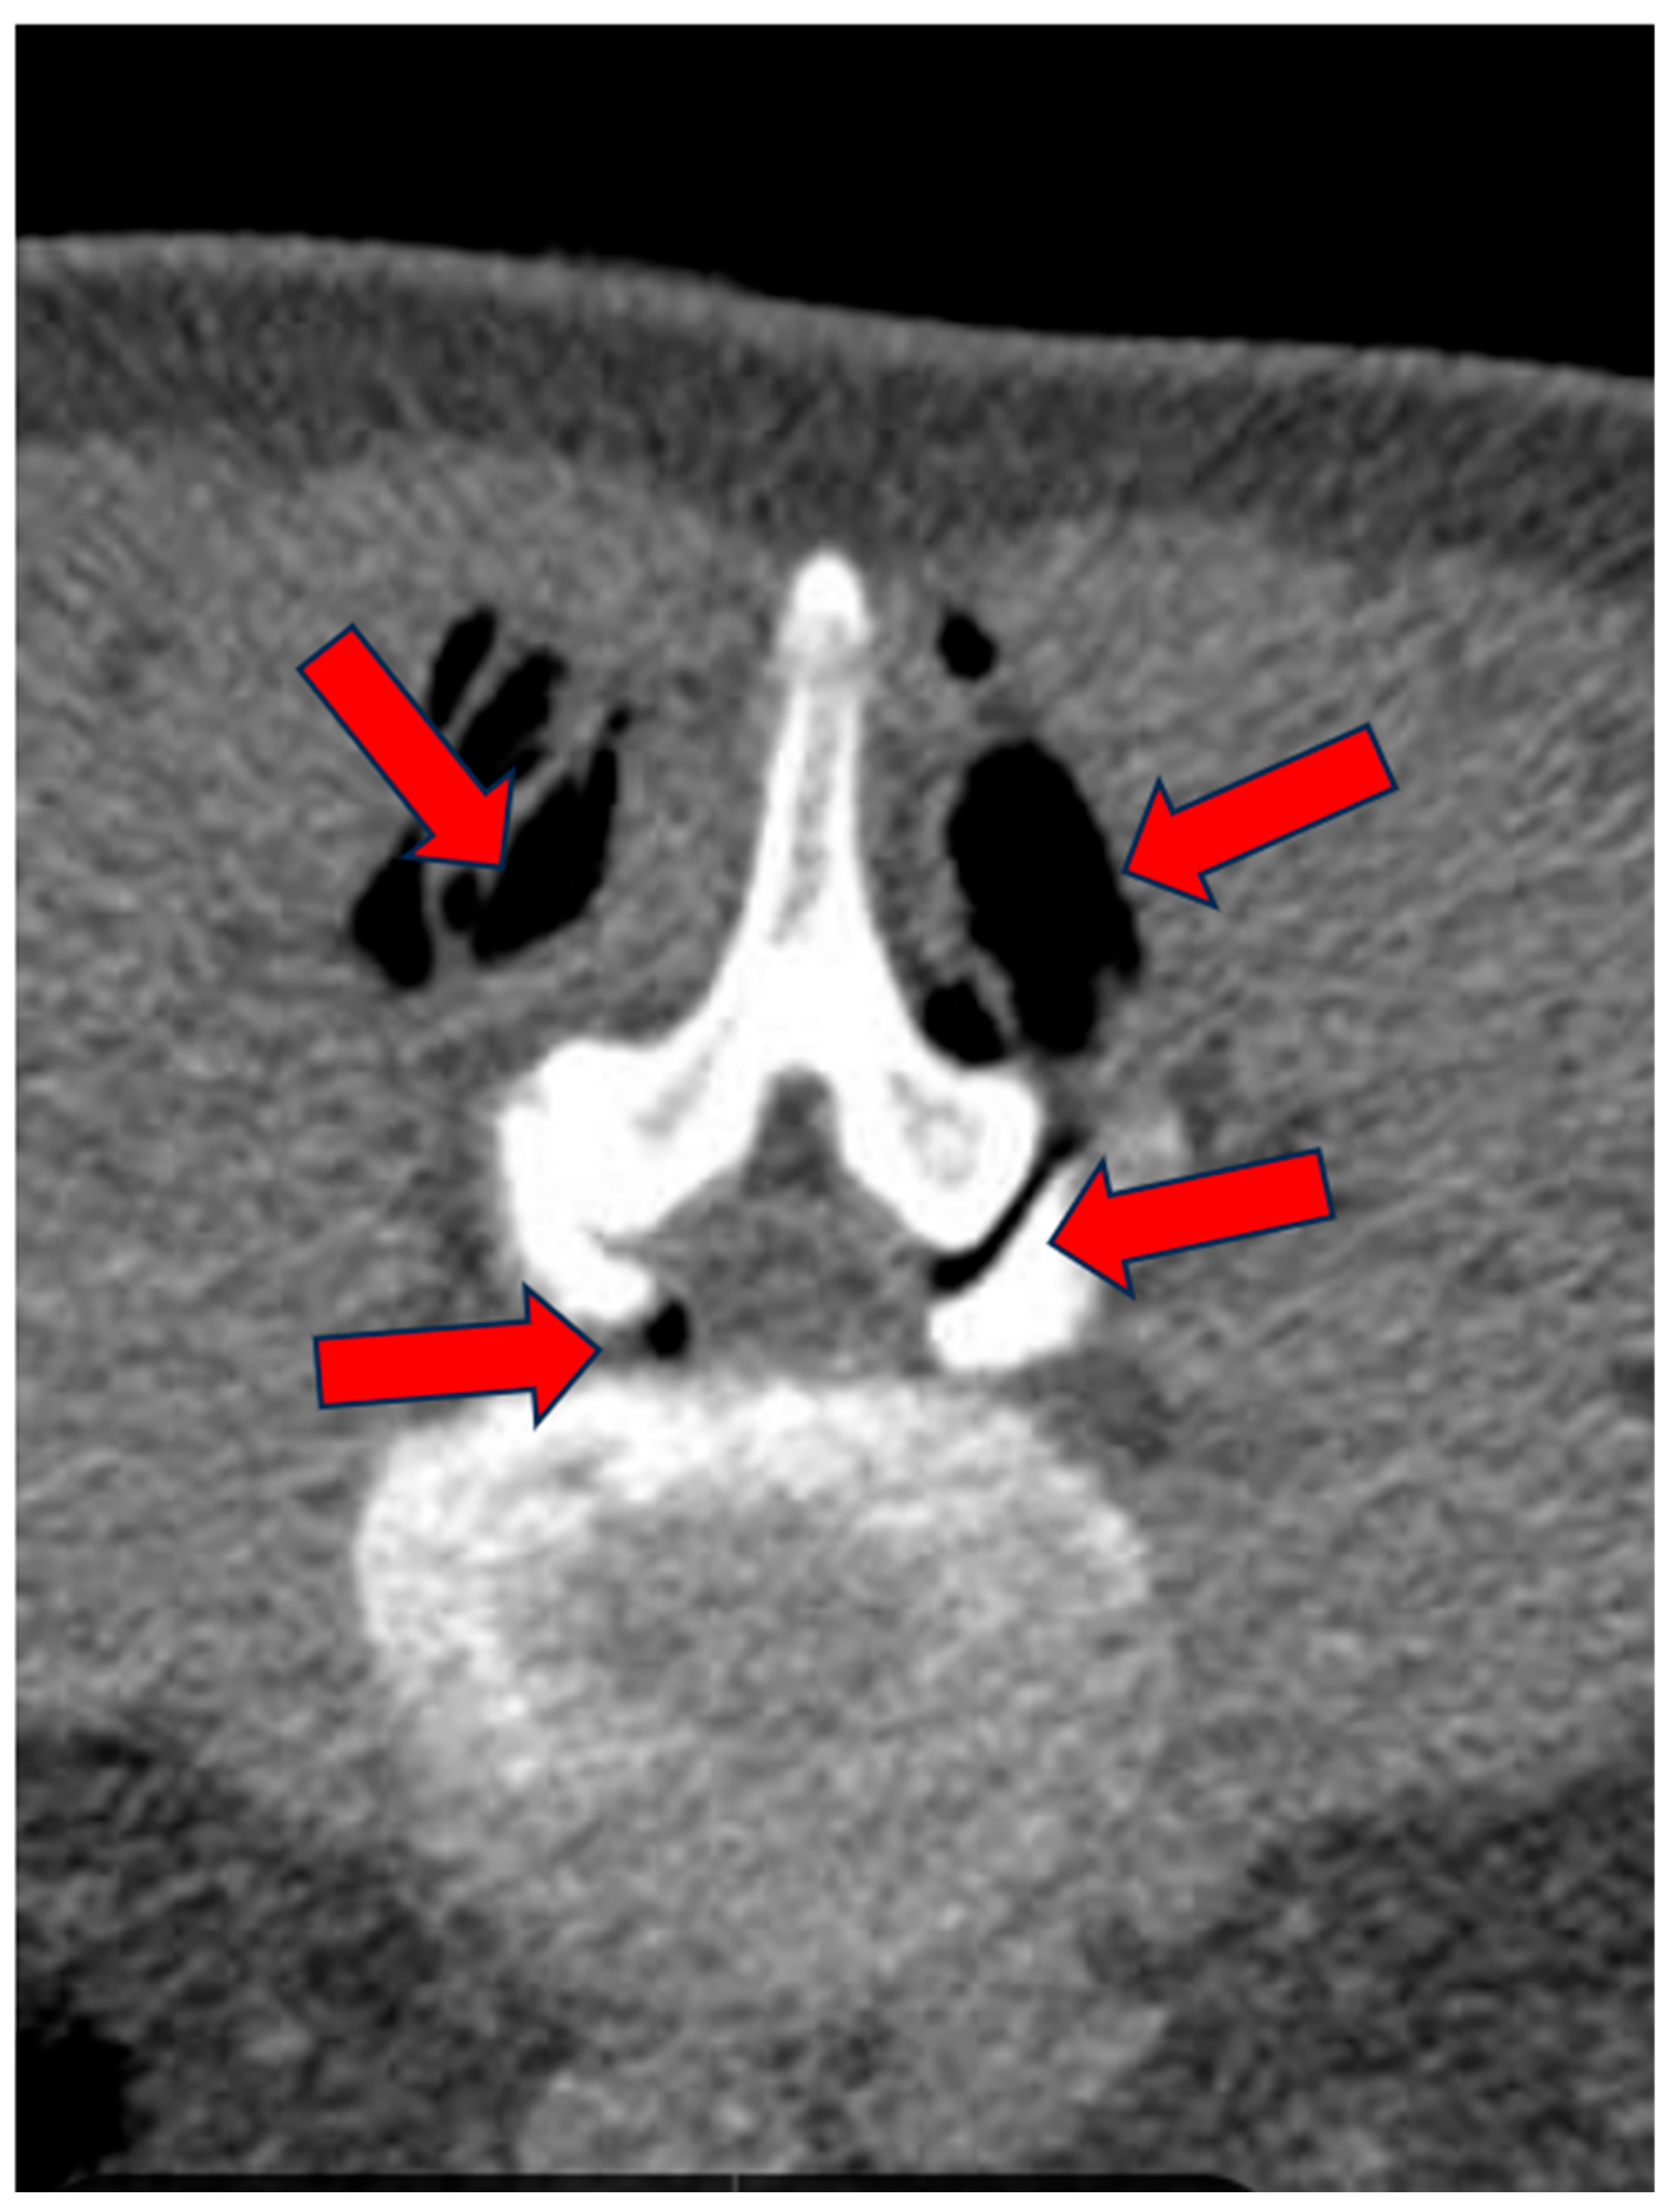

A medical record was created for each patient at enrollment, which collected key information such as age, date of birth, date of enrollment, date of treatment, and clinical details regarding the type of pain, radiation of pain, presence of paresthesias, Lasègue sign, sensitivity levels, lower limb reflexes, and plantar and dorsal extensions of the foot, as well as dorsal extension of the great toe. The study included patients suffering from advanced degenerative zygapophyseal osteoarthritis, lumbar disc disease (including multilevel), segmental canal stenosis, and pseudospondylolisthesis, with evidence from CT or MRI (Figure 1, Figure 2 and Figure 3).

Figure 2.

(A–C): CL of 88-year-old female treated at multiple levels (L3–L4 and L4–L5). At L3–L4, segmental canal stenosis related to pseudospondylolisthesis (A) (red arrows), concomitant intradiscal and foraminal left disc herniation at L3–L4 (arrow) (B), and circumferential disc protrusion at L4–L5 (red arrow) (C).